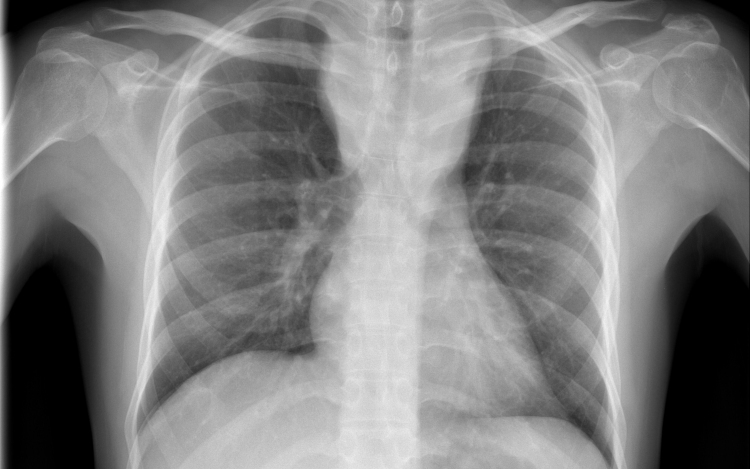

Tüdőrákban halt meg egy szervátültetett, aki egy erős dohányos tüdejét kapta meg

Tüdőrákban halt meg a transzplantáció után másfél évvel egy francia nő, akibe egy hajdan erős dohányos nő tüdejét ültették át.

A gyermekkora óta cisztás fibrózisban szenvedő páciens 2015 novemberében kapta meg a sokáig erősen dohányzó nő tüdejét, 2017 júniusában pedig bekerült a montpellier-i egyetemi klinikára, ahol két hónappal később elhunyt tüdőrákban, anélkül, hogy bármiféle terápiát alkalmazhattak volna nála. A tanulmány szerint a páciens a dohányzás okozta tüdőrák jellegzetes tüneteit mutatta.

A transzplantáció és a tüdő első rendellenességeinek röntgen általi észlelése közti rövid idő arra utal, hogy a tüdőrák már a donornál keletkezett, a szervkilökődés megakadályozására szedett immungyengítő gyógyszerek pedig csak felgyorsították a kifejlődését.